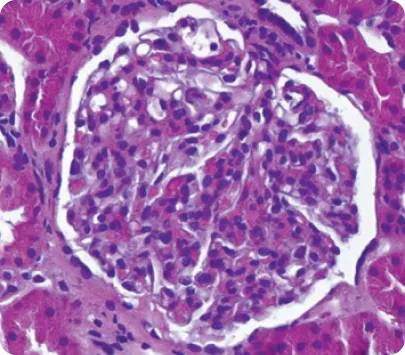

Световая микроскопия6

Image

1 -Световая микроскопия

• Световая микроскопия чаще всего не имеет высокой специфичности и не дает возможность сформировать однозначное заключение о природе почечного заболевания.

• Определяются мембранопролиферативные изменения, мезангиальная и эндокапиллярная пролиферация, а также наличие полулуний7.